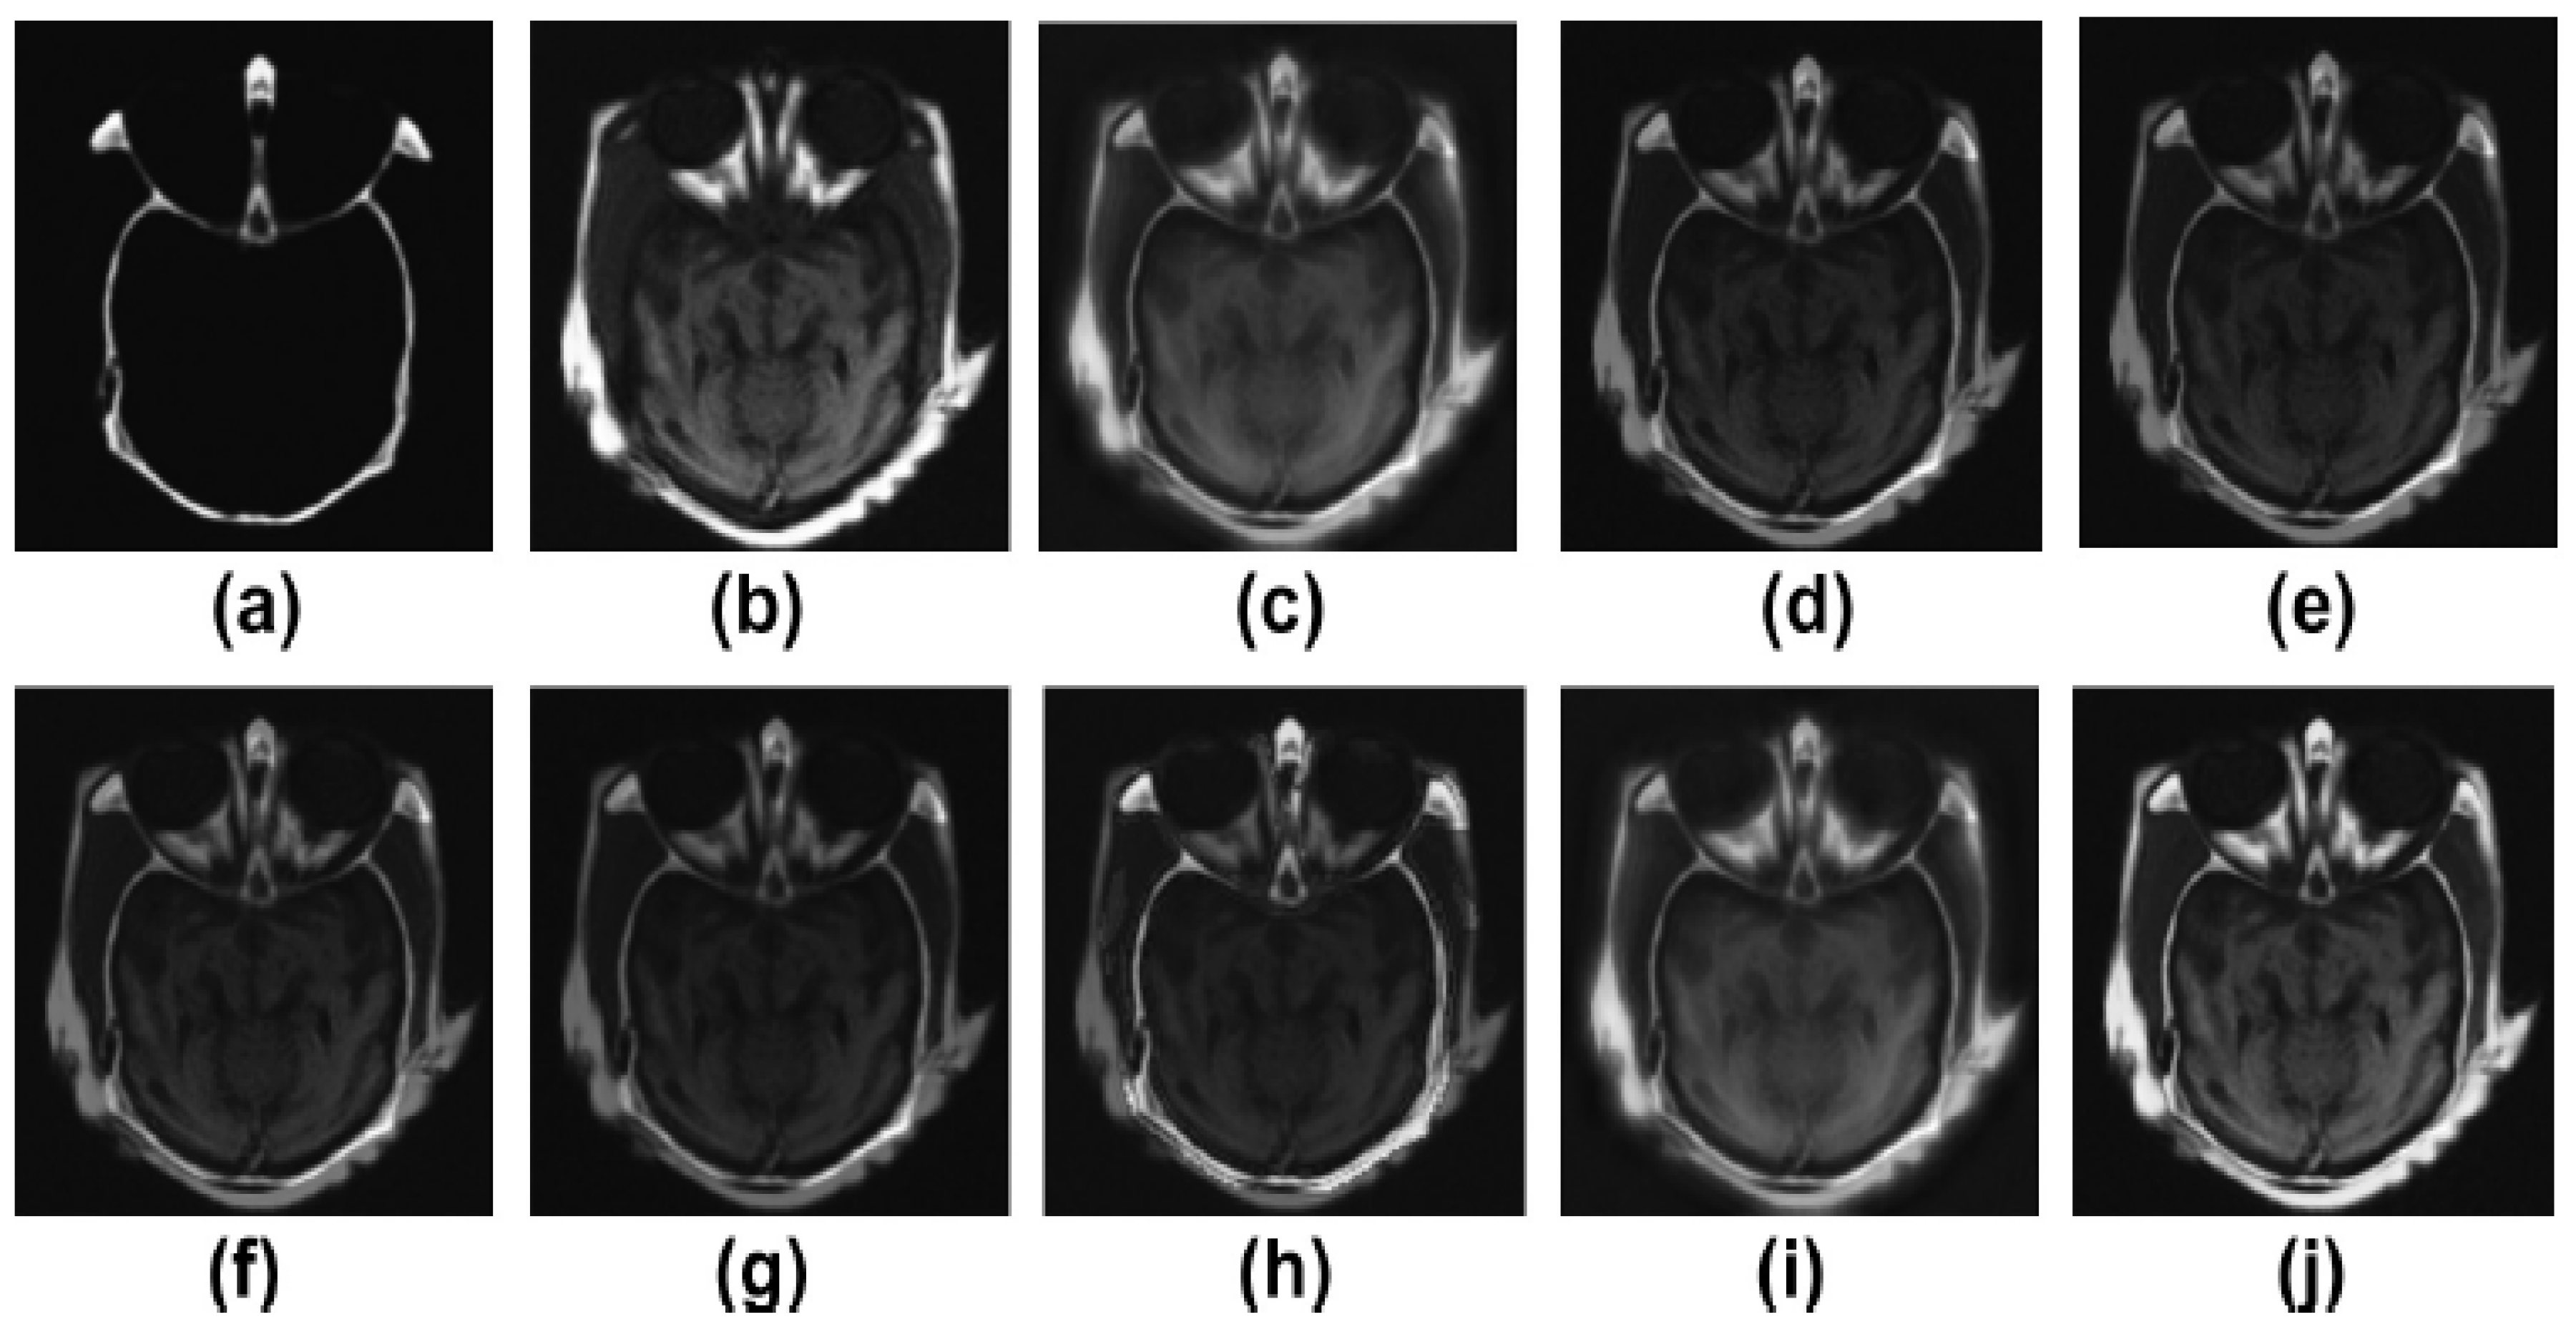

5.2. Results and Discussion